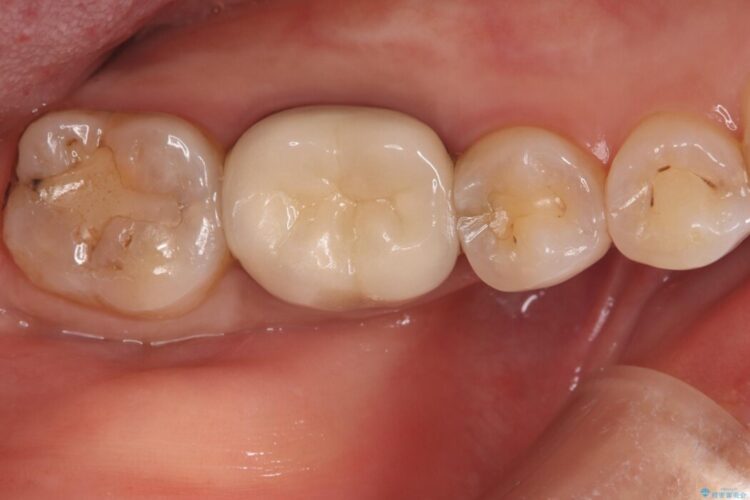

クリーニンで来院したところ、奥歯の奥側に虫歯を発見した。

診査の結果、右下7番目の歯の奥側の面や手前の歯との間にう蝕があり、噛む面にも蝕処置によるレジン材料が詰まっていました。

う蝕、古い材料を全て除去し、セラミックインレーでやり替えることとしました。